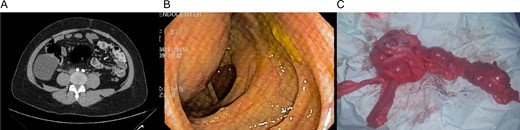

Patient is a 36-year-old woman without any past medical history, she was complaining of lower abdominal pain for about a month. Clinical examination revealed a palpable mass in the lower abdomen. A contrast-enhanced abdominal computed tomography (CT) revealed an 8 × 8 × 6 cm3 cystic lobulated mass dependent of the cecum wall, without any lymph nodes of hepatic masses (Fig. 1A). Complete blood count and laboratory exams were normal. Colonoscopy demonstrated an extrinsic compression of the lateral wall of the ascending colon. However, the mucosa and the rest of the colon appeared normal (Fig. 1B).

(A) CT revealing a 7 × 8 cm2 cystic lobulated mass dependent of the cecum wall. (B) Colonoscopy showing extrinsic compression of the lateral wall of the ascending colon. (C) Colonic mass and right colon.

Since the pain continued to persist, surgery was planned and a laparoscopic approach was decided. A 8 × 7 × 6 cm3 cystic mass was discovered that covered and was completely attached to the cecum and ascending colon, no vascular pedicle was identified and no lymph nodes or other masses were found, in light of this, a right laparoscopic hemicolectomy was performed with autosutures (Supplementary Video).

The right colon with the mass was completely resected through a small midline incision without complications. The external surface of the mass was pinkish-gray color and the cystic wall was even in thickness ~0.4 cm (Fig. 1C) and contained clear mucous fluid. Pathology reported intestinal duplication cyst, microscopically, the cystic wall partially consisted of normal mucosa, submucosa, smooth muscle and serosa (Fig. 2A and B). No epithelial dysplasia or malignancy was evident.